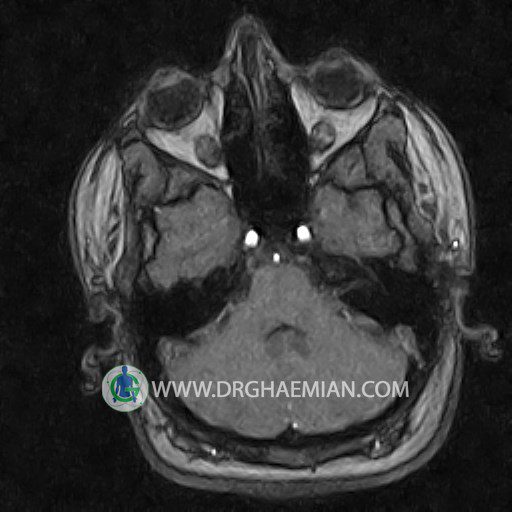

CRANIAL MRV

Technique: TOF ( time of flight ).

Images of the venous cranial vessels demonstrates a superior sagittal sinus of normal caliber with normal arrangement of draining superficial cerebral veins.

The great cerebral vein Galen inferior sagittal , straight sinus and left sigmoid sinuses appear normal.

The right transverse and sigmoid sinuses present a normal caliber.

The other evaluable deep cerebral veins , basal and labbe are normally developed and patent.

– Narrowing of left transverse sinus without inthimal irregularity & without filling defect suggestive for cengenital hypoplasia

– Two high signal focus ( 9 mm & 11 mm in diameter ) in left internal capsule suggestive for ischemic foci & low grade glioma

are seen